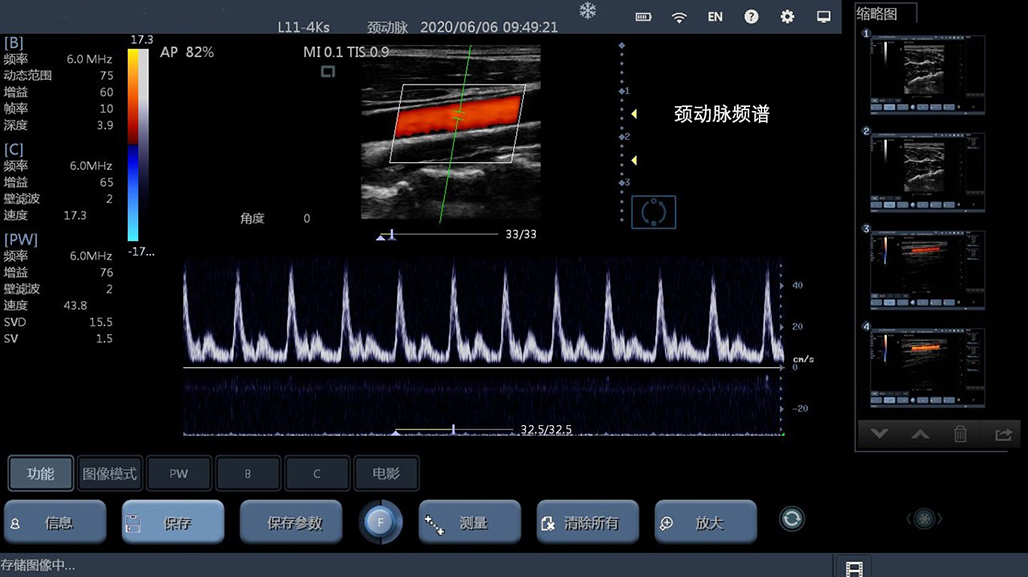

• 线阵

甲状腺

血管

神经

肌骨等